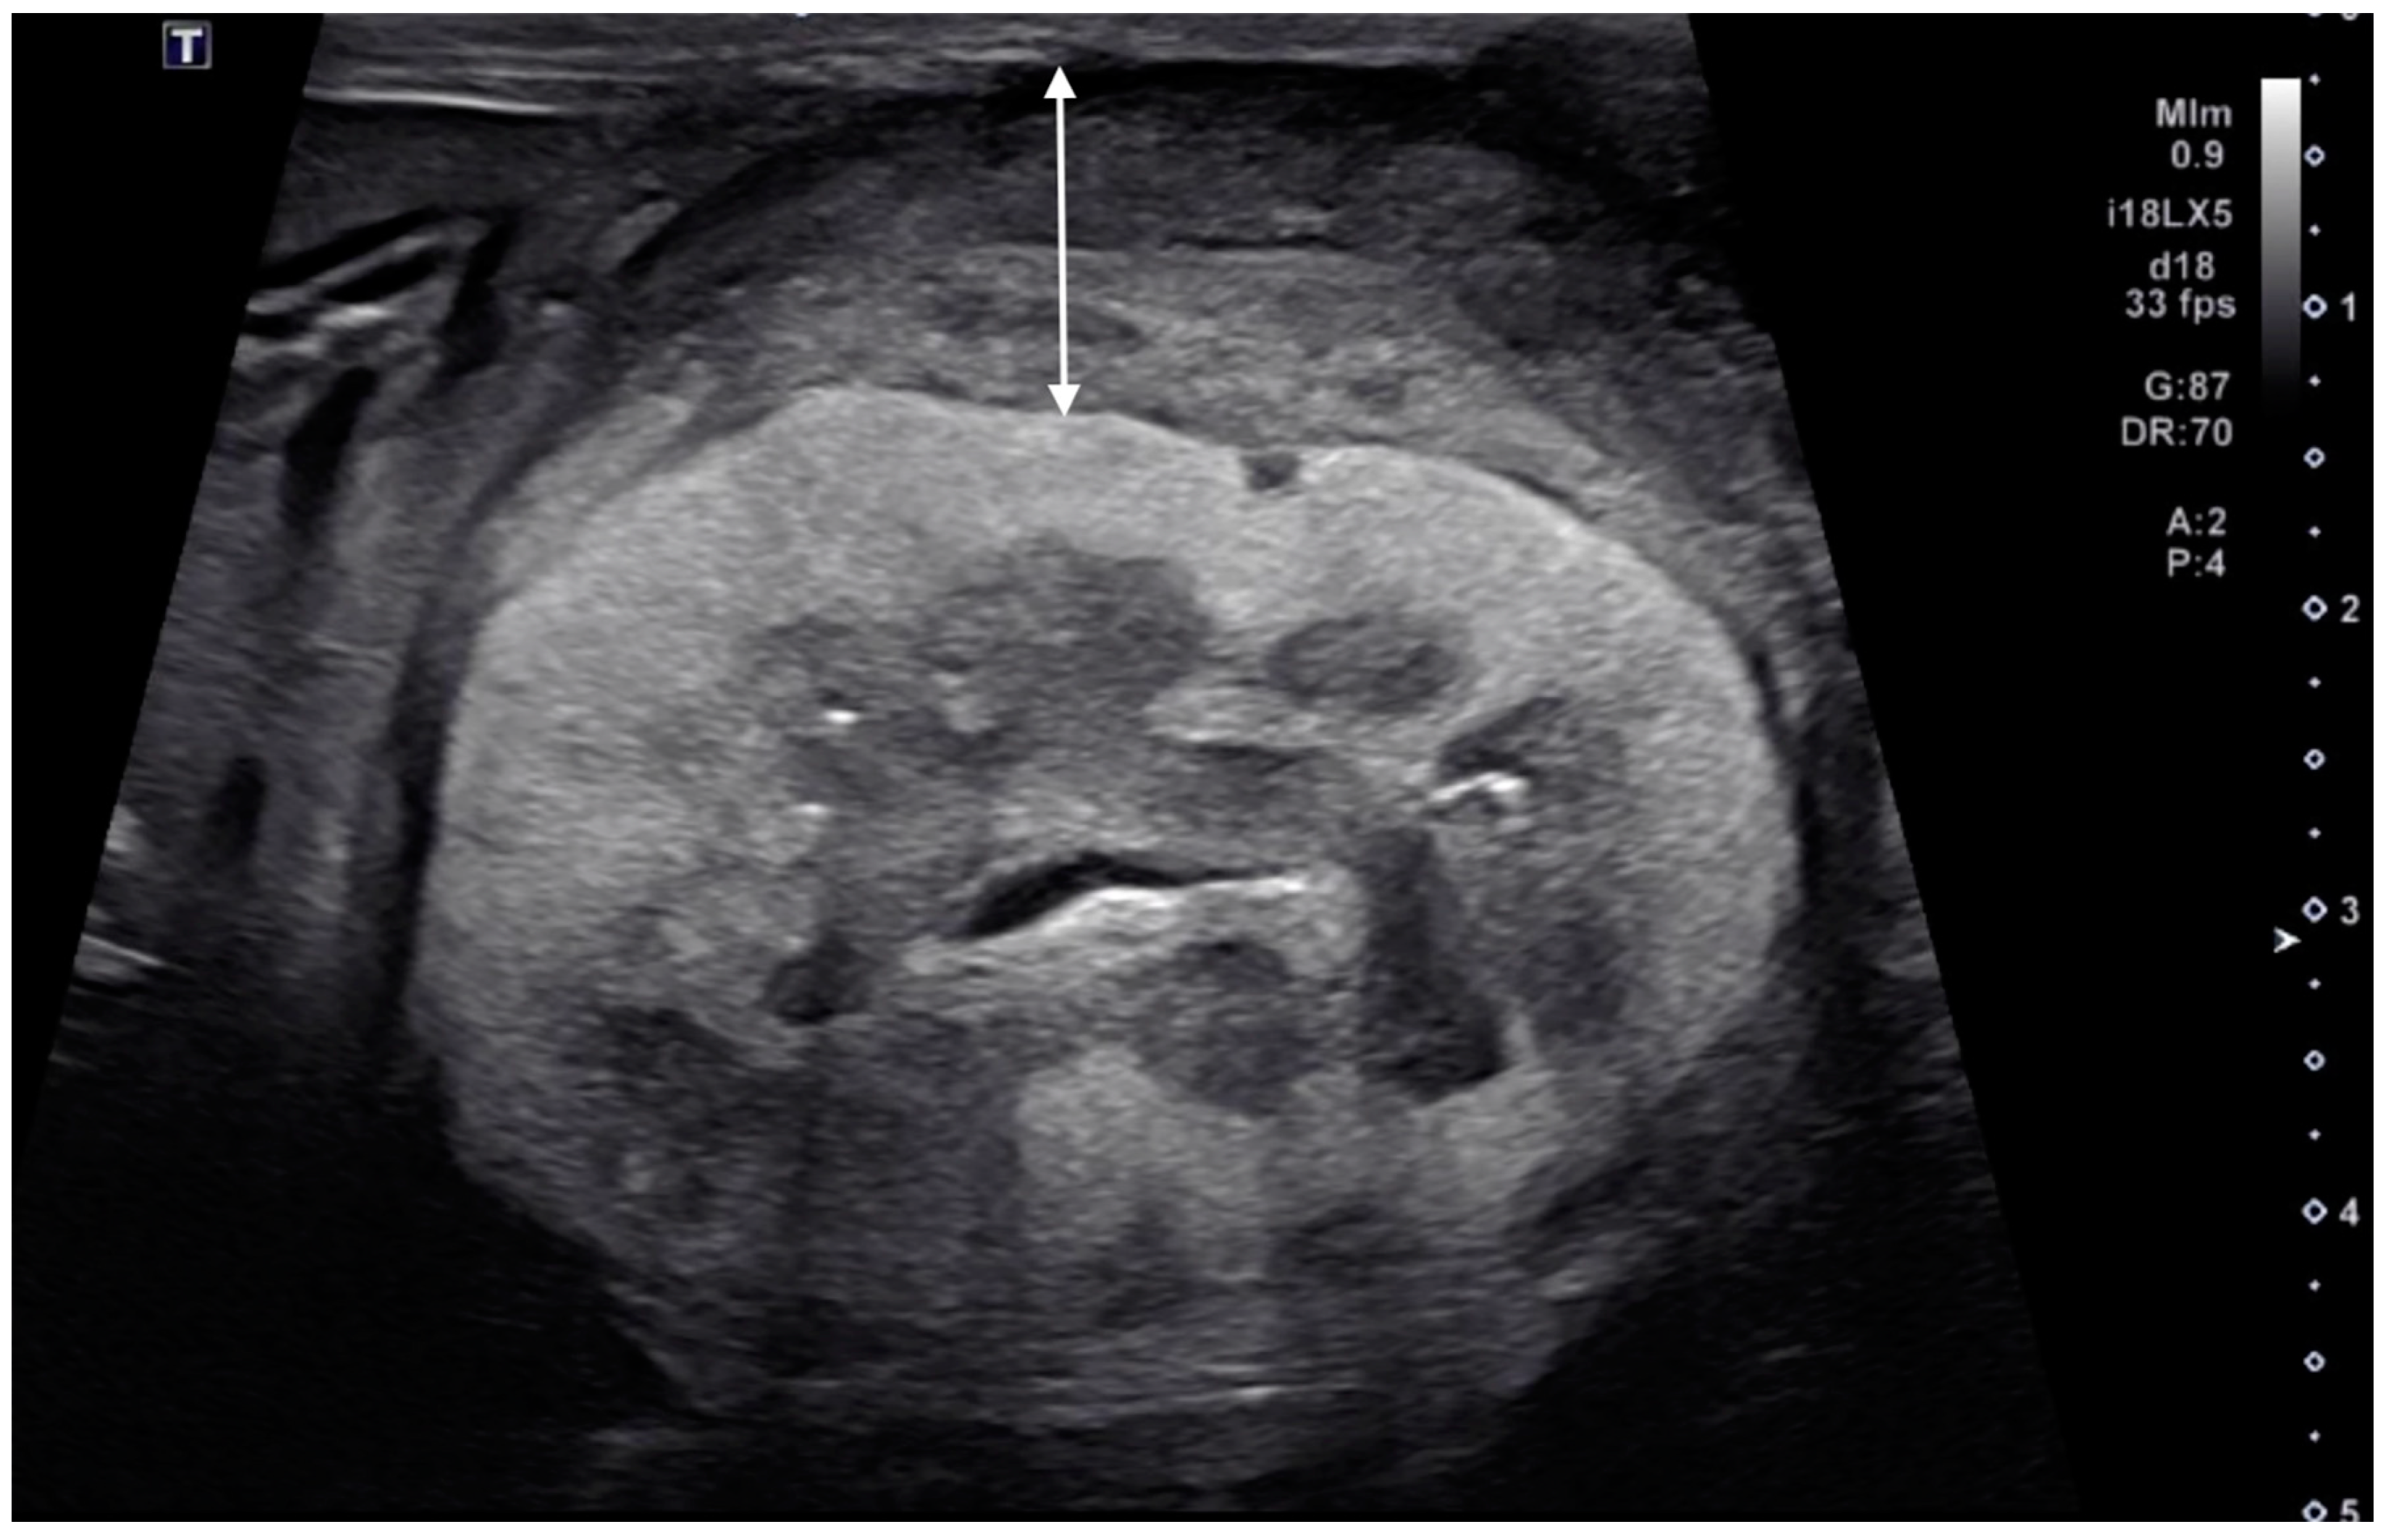

3.3. Ultrasonographic Findings of Subcapsular Thickening

3.4. Ultrasonographic Findings of the Rest of the Kidney

| Distribution | Maximum Thickness (mm) | Echotexture | Echogenicity | Renal Cortical Margin | Renal Capsular Margin | Vascularity | Perirenal Effusion | Architecture | Characteristic Pattern | Corticomedullary Distinction | Renal Pelvis Diameter (mm) | Mineralization | Cystic Lesion | Nodule | |||||

| 1 | 10 year-old, MN, DSH | left | focal | 3.5 | homo | hypo | irregular | irregular | no | no | normal | ill-defined | 1.3 | no | no | yes | Metastatic Carcinoma and Suspected Metastatic Carcinoma (sample obtained from either right or left kidney) | Pulmonary Carcinoma (lung, muscle) | |

| right | focal | 3.5 | homo | hypo | irregular | irregular | no | no | abnormal | hypoechoic striations within hyperechoic areas | ill-defined | no dilation | no | no | no | ||||

| 3 | 11 year-old, MN, DSH | right | focal | 2.8 | homo | hypo | irregular | smooth | yes | no | abnormal | ill-defined | no dilation | no | no | yes | Suspected Metastatic Carcinoma | Pulmonary Carcinoma (lung) | |

| 4 | 9 year-old, FN, DSH | left | focal | 4.8 | homo | hypo | irregular | irregular | no | no | abnormal | hypoechoic striations within hyperechoic areas | ill-defined | no dilation | no | no | no | Metastatic Carcinoma | Pulmonary Carcinoma (lung) |